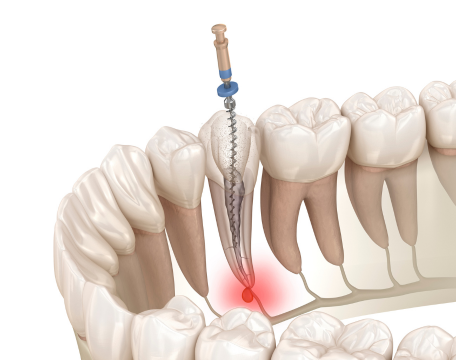

単に虫歯を治す、歯周病をケアする、歯を白くするといった部分的な治療に留まらず、なぜその症状が起きたのか、その根本原因を探ることを重視しています。

多くの場合、その原因は「咬み合わせの不調和」にあるのです。

当院では虫歯や歯周病の治療はもちろん、顎関節症や咬合治療、矯正、義歯、インプラントなど多岐にわたる治療を行っております。